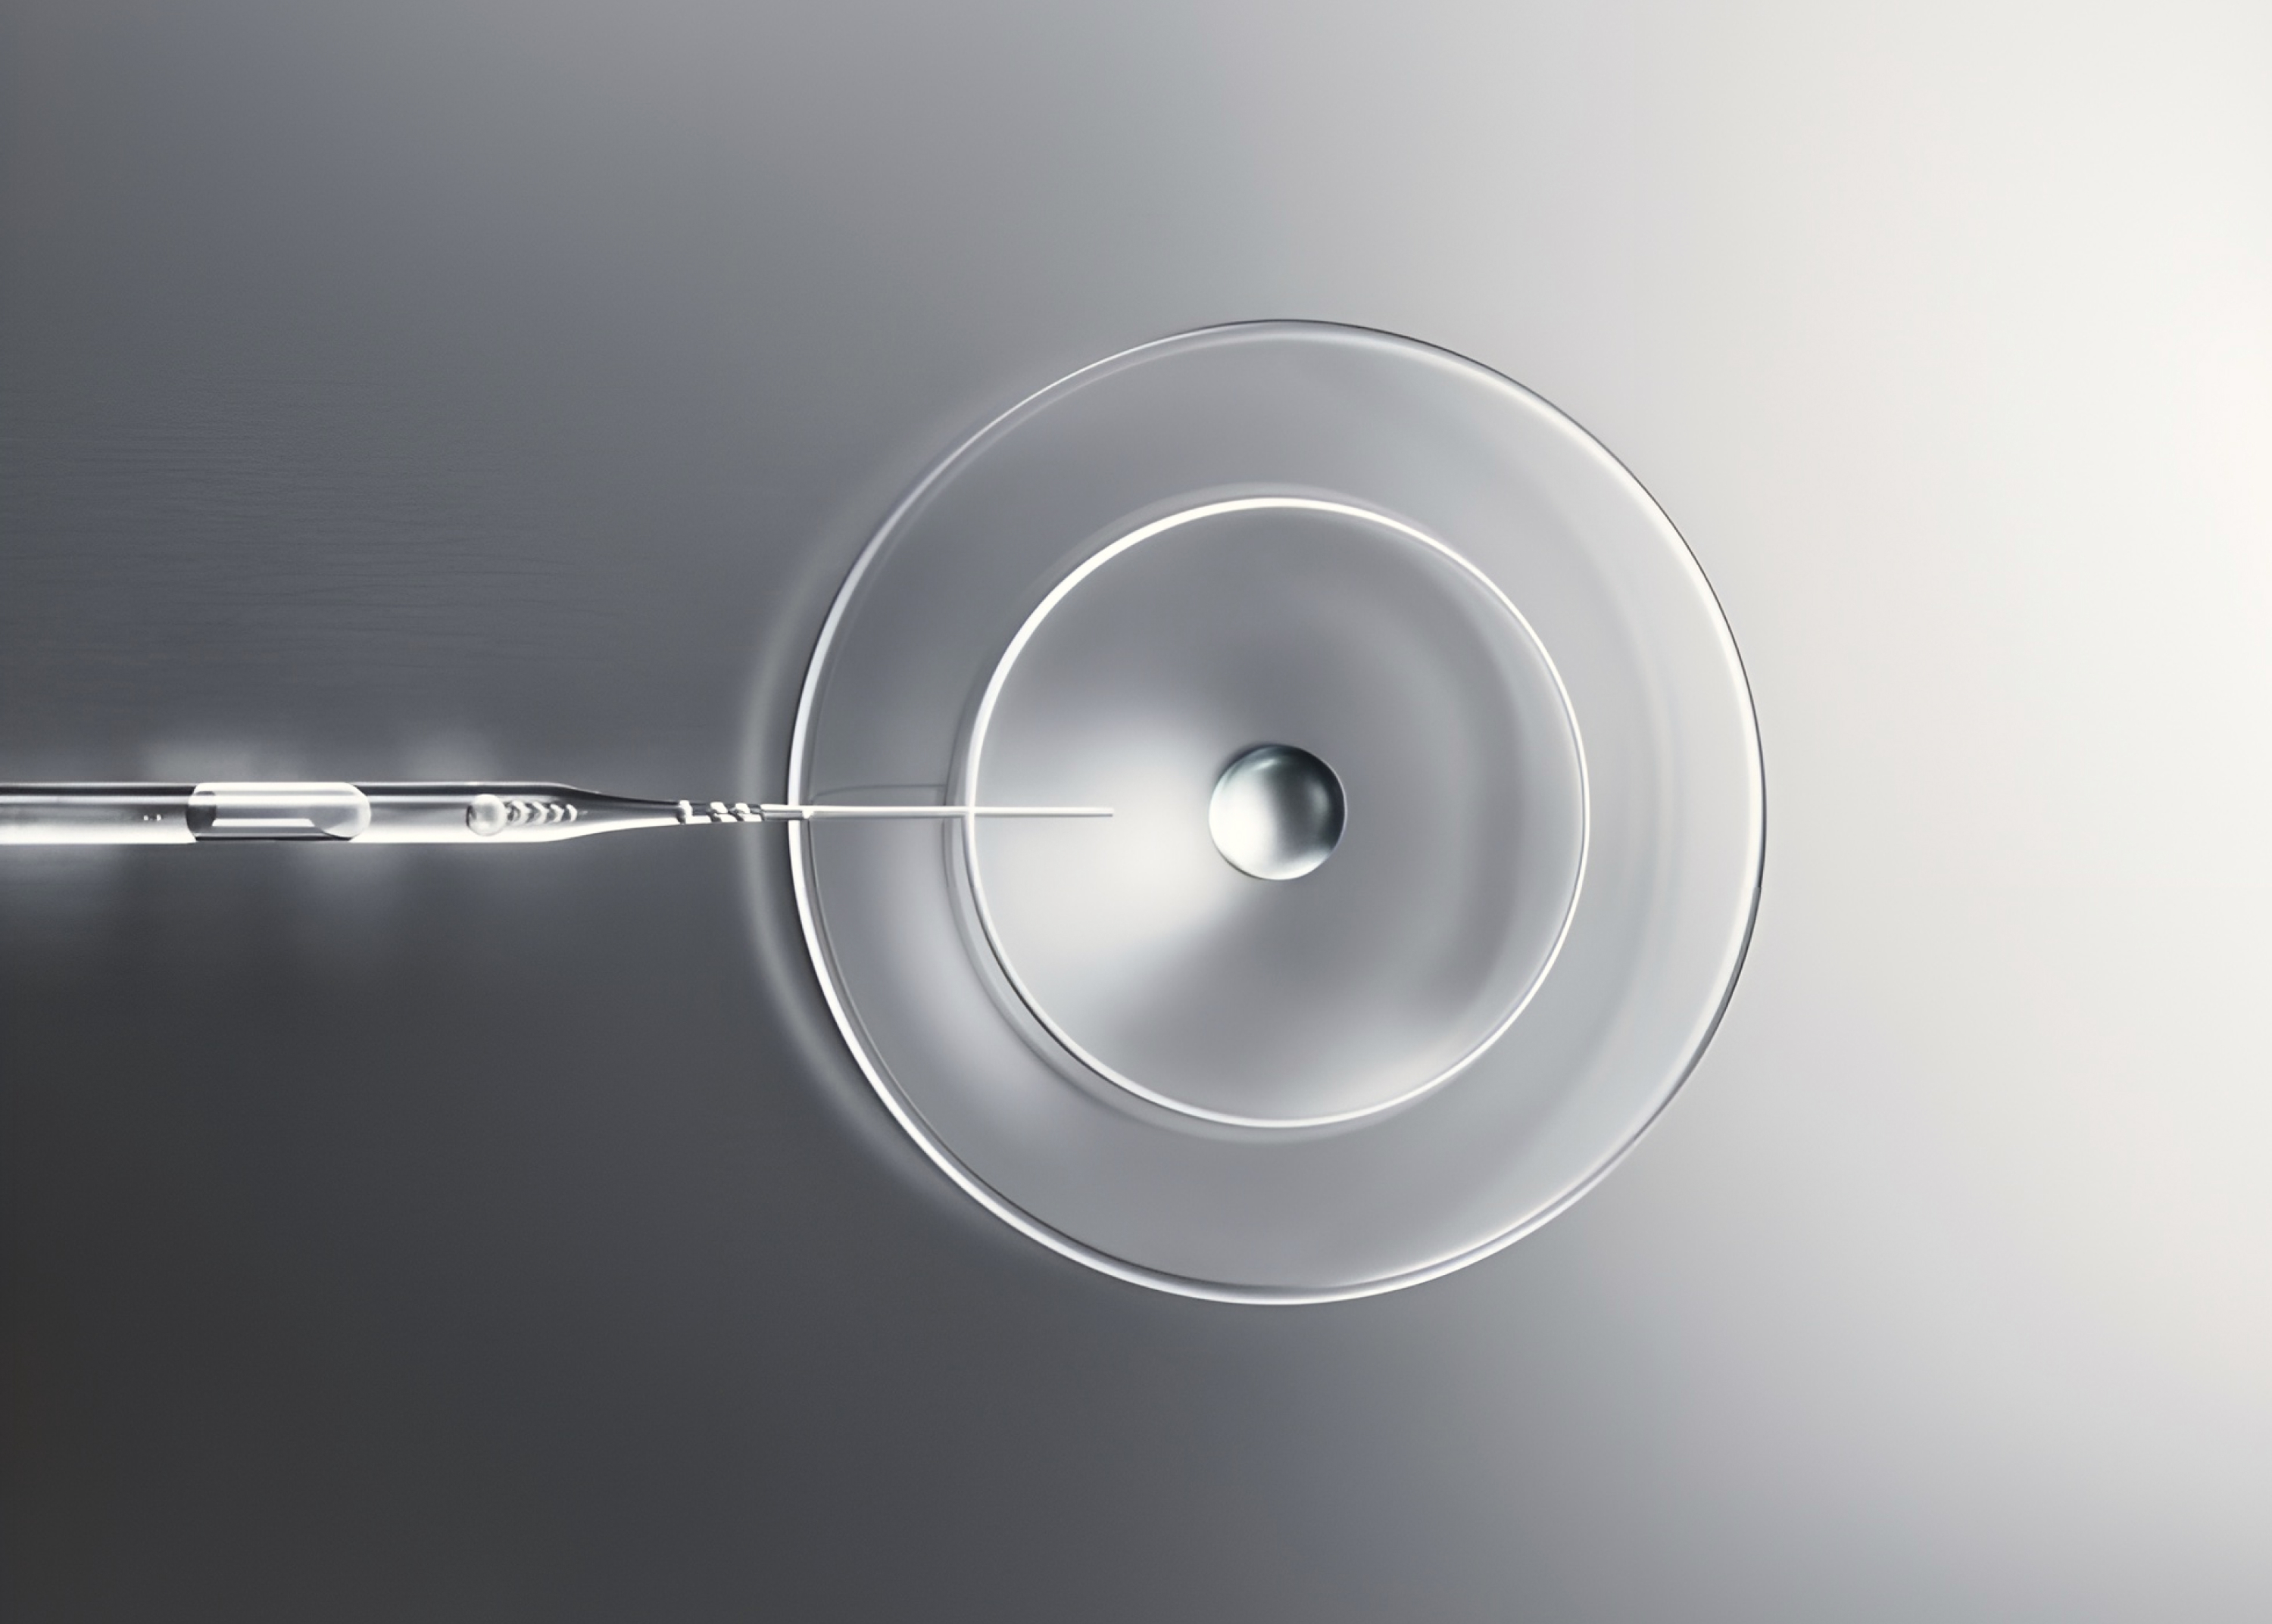

▪️Ключевые аспекты эффективной работы с линейкой нативного коллагена Collost.

▪️Фокус на периорбиту - практические аспекты успешной работы.

▪️Дозировки, техники, нюансы применения.